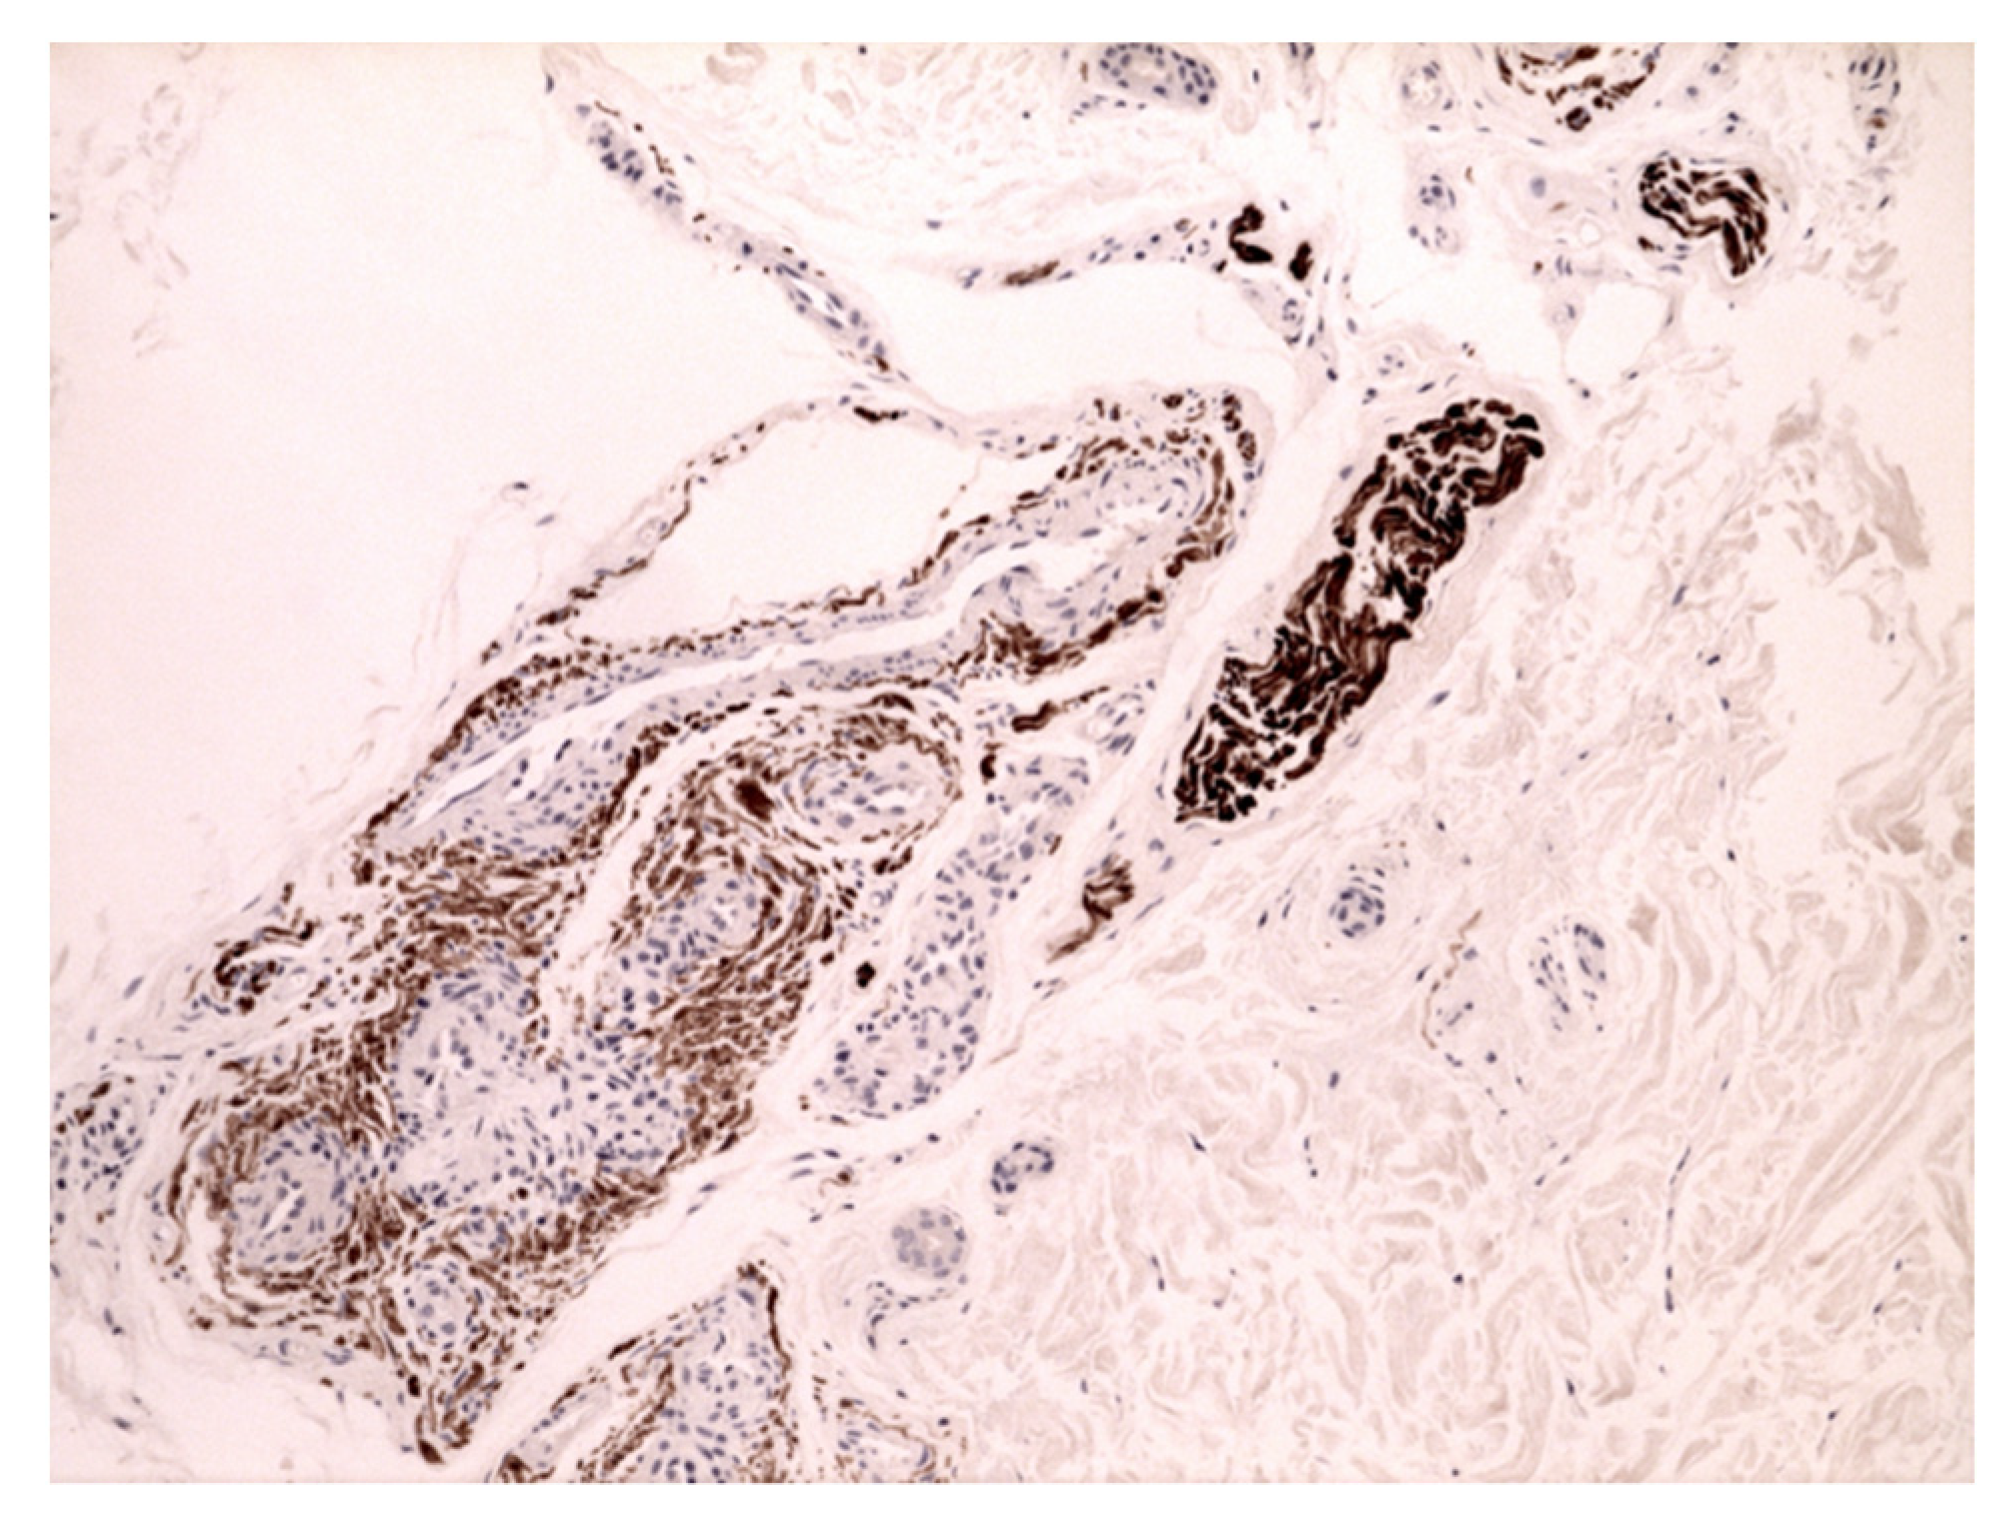

- Marušić, Z.; Korša, L.; Calonje, E. Dermal hyperneury. Clin. Dermatol. 2021, 39, 291–294. [Google Scholar] [CrossRef]

- Ieremia, E.; Marušić, Z.; Mudaliar, V.; Kelly, S.; Rodriguez, P.G.; McNiff, J.M.; LeBoit, P.E.; Calonje, E. Expanding the clinical spectrum of dermal hyperneury: Report of nine new cases and a review of the literature. Histopathology 2019, 75, 738–745. [Google Scholar] [CrossRef] [PubMed]